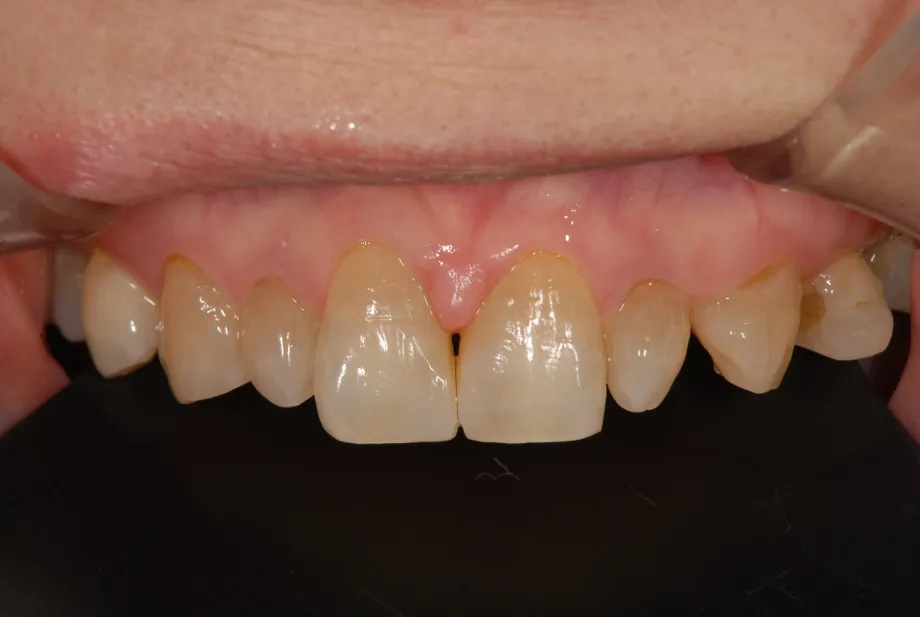

CASE1 60代女性 ダイレクトボンディングによる修復治療

初診

歯石除去で来院されました。

除去後、話を聞くと上顎の前歯の歯と歯の間が離れていることが

以前より気になっていると仰られ、治療計画を立案。

レントゲン写真を撮影。

口腔内写真の撮影

残っている歯の問題点などを解析

顔全体・口元の写真を解析

前方・口元

側方・口元

口腔内の分析・治療計画

さまざまな方向性から、歯のバランスや問題点を解析。

治療計画の立案を行います。

治療後

治療その後

術後4ヶ月